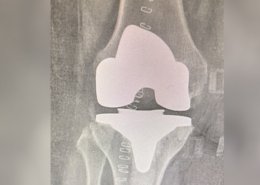

Dr. Shiva Shankaran GB is a senior specialist surgeon in knee and shoulder surgeries. He specializes in Sports injury, Arthroscopy, and Joint Replacement Surgeries. His journey is marked by a commitment to excellence and a relentless pursuit of knowledge. Physical Remedy and drugs are the first non-surgical options we look into when treating common pain, but if surgery is eventually necessary, we’ll give you the best treatment possible to help you return to your diurnal conditioning as soon as possible.

Arthroscopic & Replacement Surgeries